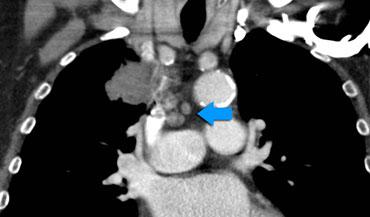

Ví dụ: Khối u bên phải với di căn hạch tại nhiều trạm trung thất cùng bên (4R và 2R) được phân loại là N2b.

Hạch N3

Hạch N3 đại diện cho bệnh lý hạch trung thất hoặc rốn phổi đối bên, hoặc hạch cơ bậc thang hoặc hạch thượng đòn, và được xem là không thể phẫu thuật cắt bỏ.

Ví dụ:

Khối u bên phải với di căn hạch N3, bao gồm các trạm trung thất đối bên 4L và 5.

Các hình ảnh này thuộc về hai bệnh nhân khác nhau bị ung thư phổi ở phổi phải.

Hình ảnh

Có các hạch bạch huyết ở phía đối bên.

Nếu các hạch bạch huyết này chứa tế bào ung thư, điều đó có nghĩa là bệnh giai đoạn N3.